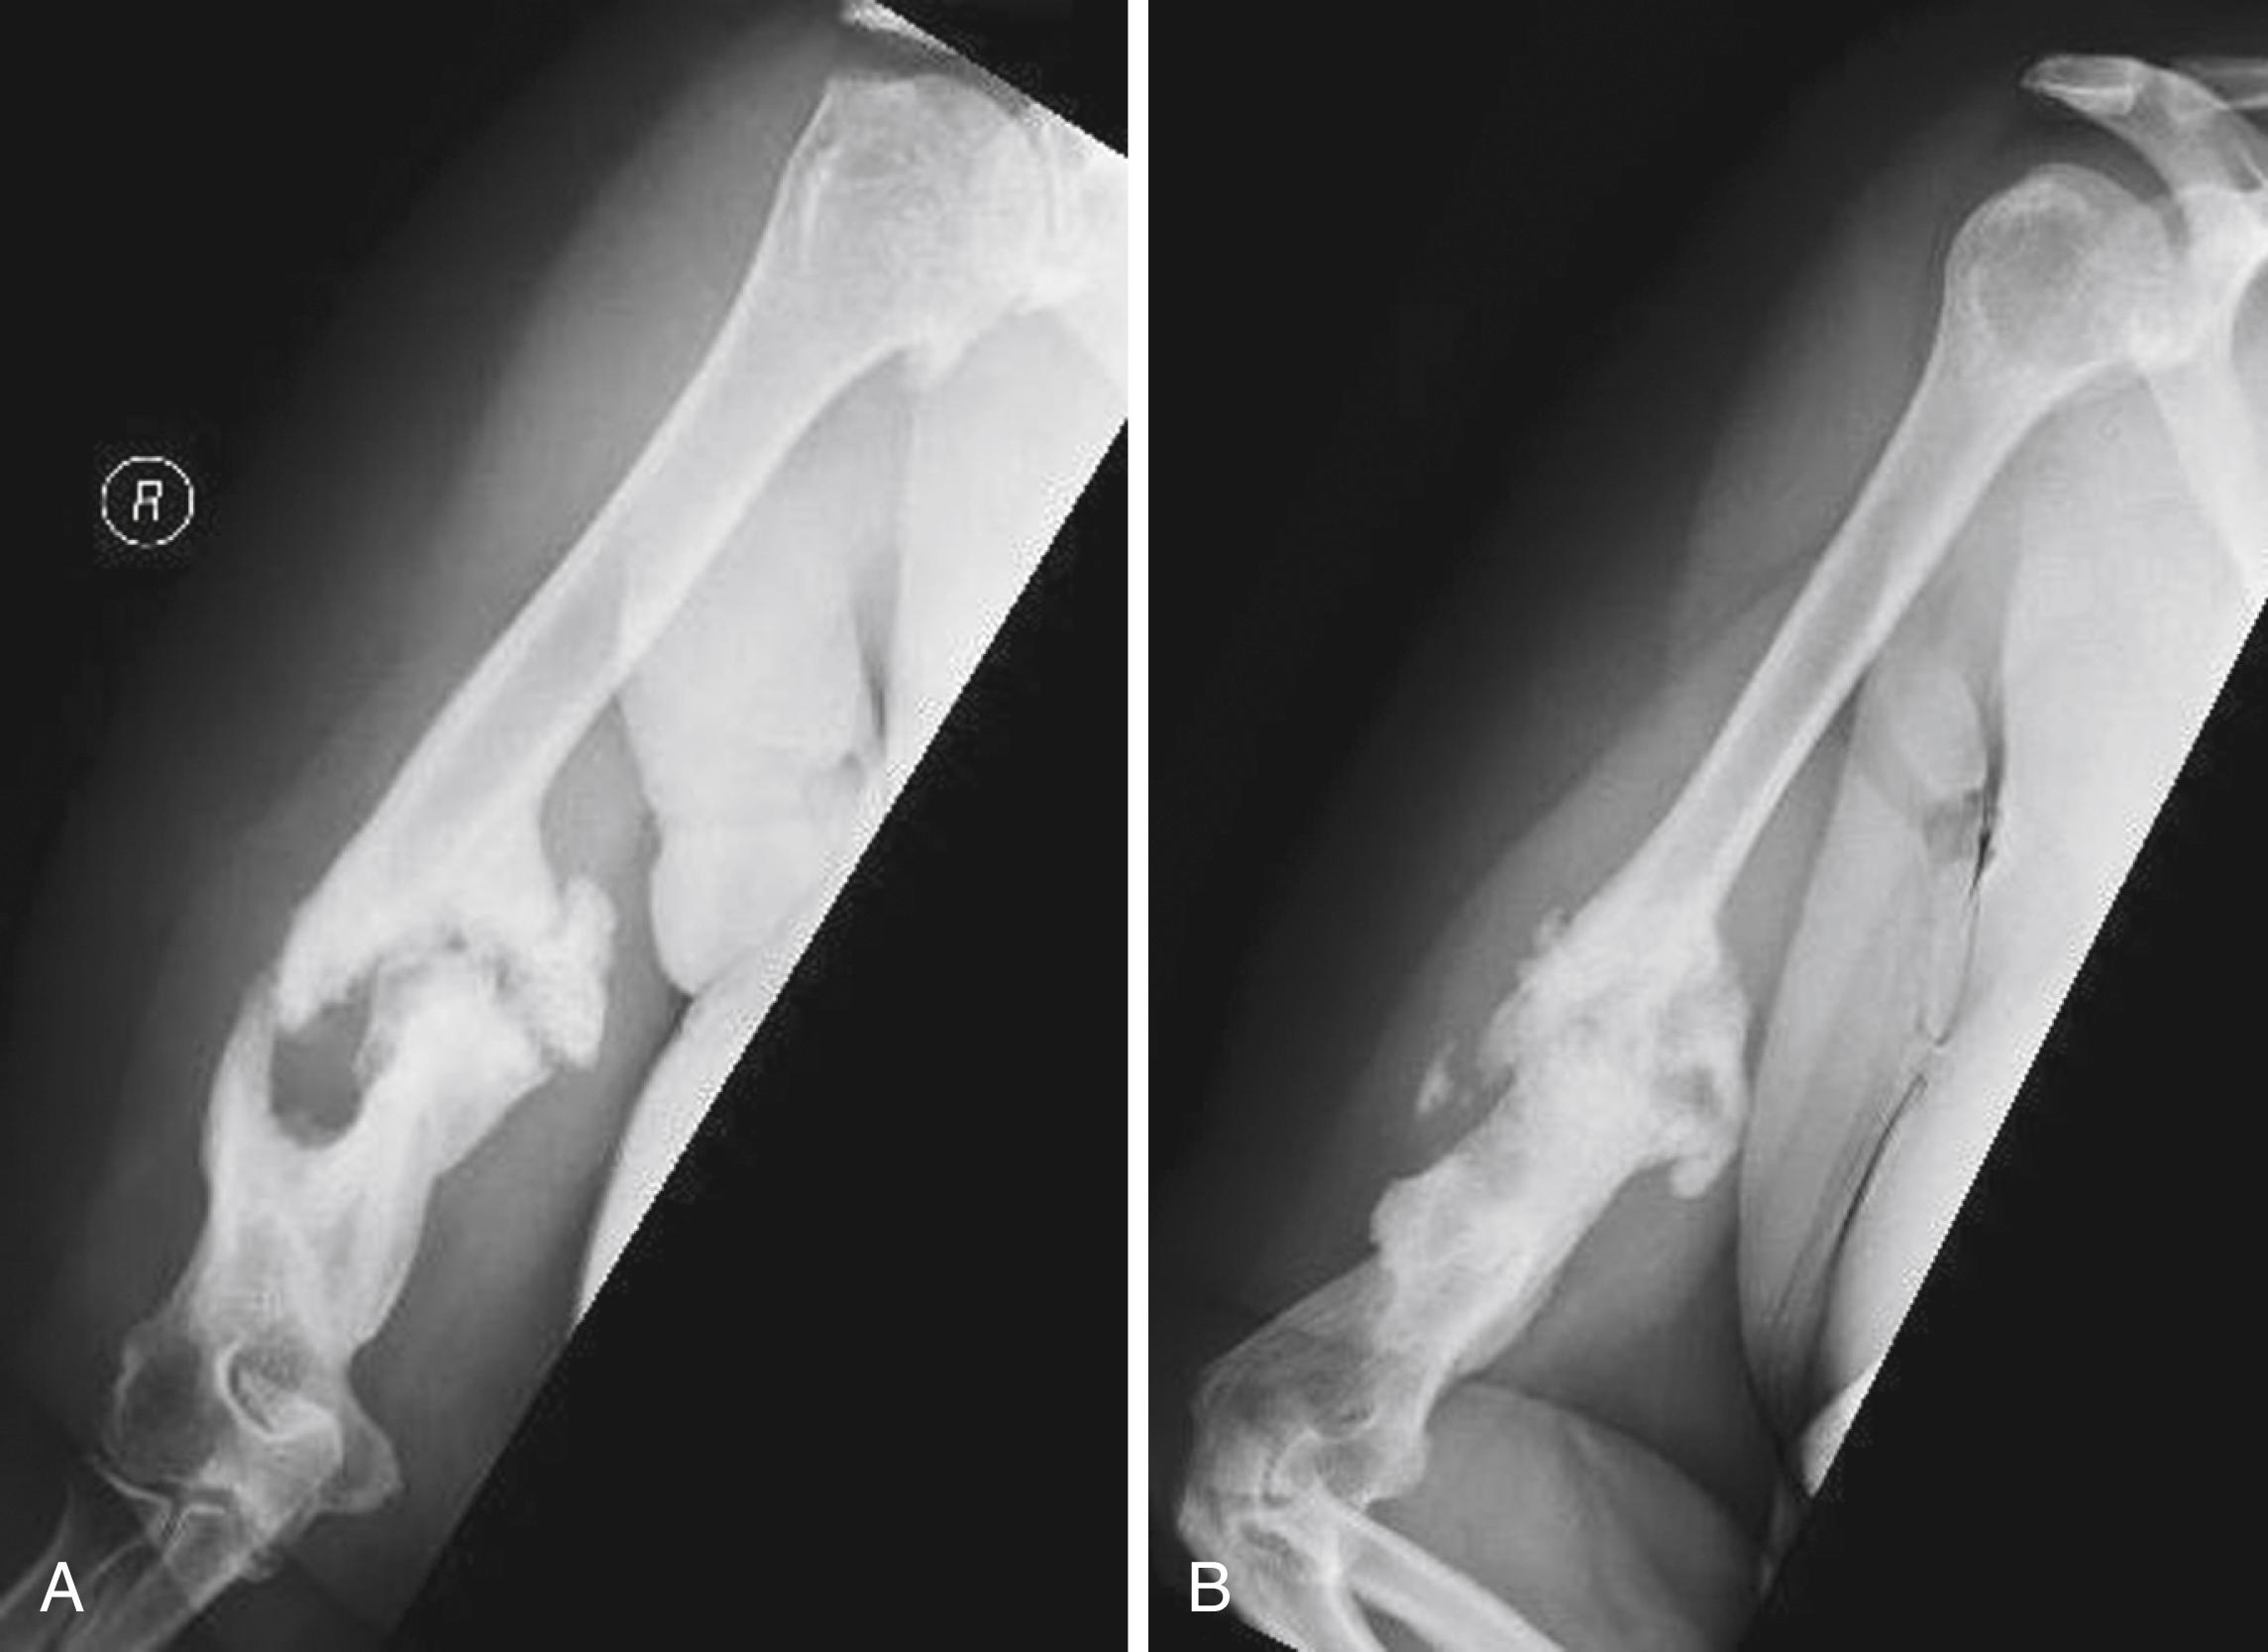

Septic nonunions are much more difficult to treat than aseptic nonunions. Hypertrophic nonunions ( Fig. 59.4 ) have adequate vascularity, display abundant callus, and lack stability. Oligotrophic nonunions usually have adequate vascularity, display little or no callus, and often are associated with malreduction (distraction). Atrophic nonunions ( Fig. 59.5 ) lack adequate vascularity and display no callus. Synovial pseudarthrosis ( Fig. 59.6 ) involves sealed medullary canals with an associated pseudomembrane containing fluid. Radiographic appearance is variable, and technetium bone scan reveals a “cold cleft” between areas of increased activity. Classification of nonunions has historically guided treatment and is therefore important to understand.

FIGURE 59.4, A and B, Hypertrophic humeral nonunion.